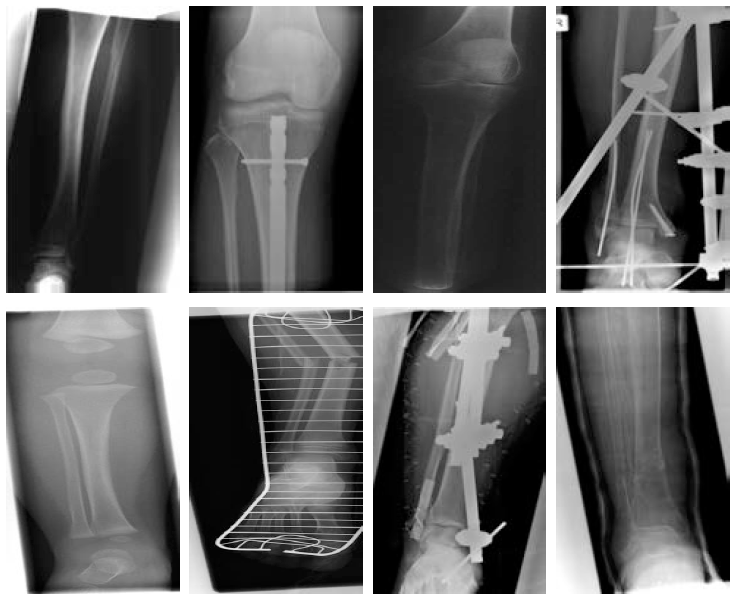

IV-E Visual Examples

Some query-by-example experiments are implemented in this part. Figure 8 illustrates some samples with correctly classified categories. The images on the left hand side in each row are the original query images and on the right hand side are top 5 retrieved images based on the Hamming distance of the Radon barcodes. The results demonstrate that the proposed method has the ability to retrieve similar images from the same category as long as the class of the query image is identified correctly.

The query-by-example experiment with regard to the wrongly classified samples by SVM are presented in Figure 9. The results show that even if the class of the query images cannot be correctly identified by SVM, the retrieved responses may still be visually similar to the input image. Some of the retrieved images shown in Figure 9 are supposed to be in the same category as the query ones, which implies that more accurate labeling of the dataset will improve the performance of the proposed approach. Therefore, we can conclude that our method depends on the a performance of the classifier but not limited by it.

Figure 8: Results of query-by-example experiment for correctly identified query

Figure 9: Results of query-by-example experiment for wrongly identified query